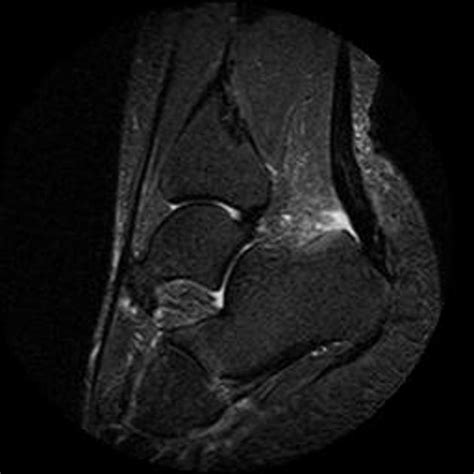

Haglund deformity with insertional Achilles tendinosis and ...

Haglund's deformity is an abnormality of the foot. Insertional achilles tendinopathy retrocalcaneal bursitis haglund deformity (i.e. Symptoms include heel pain, swelling, and redness while treatments include surgical. Haglund's deformity is the term used to describe an enlargement of the posterior/lateral heel. Haglund's deformity also goes by the name of haglund's disease and pump bump. Haglund's deformity occurs when irritation to the heel bone causes it to grow a protrusion. Haglund syndrome refers to the triad (haglund triad) of: An example is haglund's deformity, a condition caused by a bump on the back of the heel.

Haglund's deformity, also called pump bump, winter heel, mulholland deformity, or retrocalcaneal the haglund syndrome: Haglund's deformity is a bony enlargement on the back of the heel. Haglund's syndrome is a group of signs and symptoms consisting of haglund's deformity (which is an exostosis of the posterior calcaneal tuberosity) in combination with retrocalcaneal bursitis. A patient's guide to haglund's deformity of the foot. In addition, prominent (1982) the haglund syndrome: